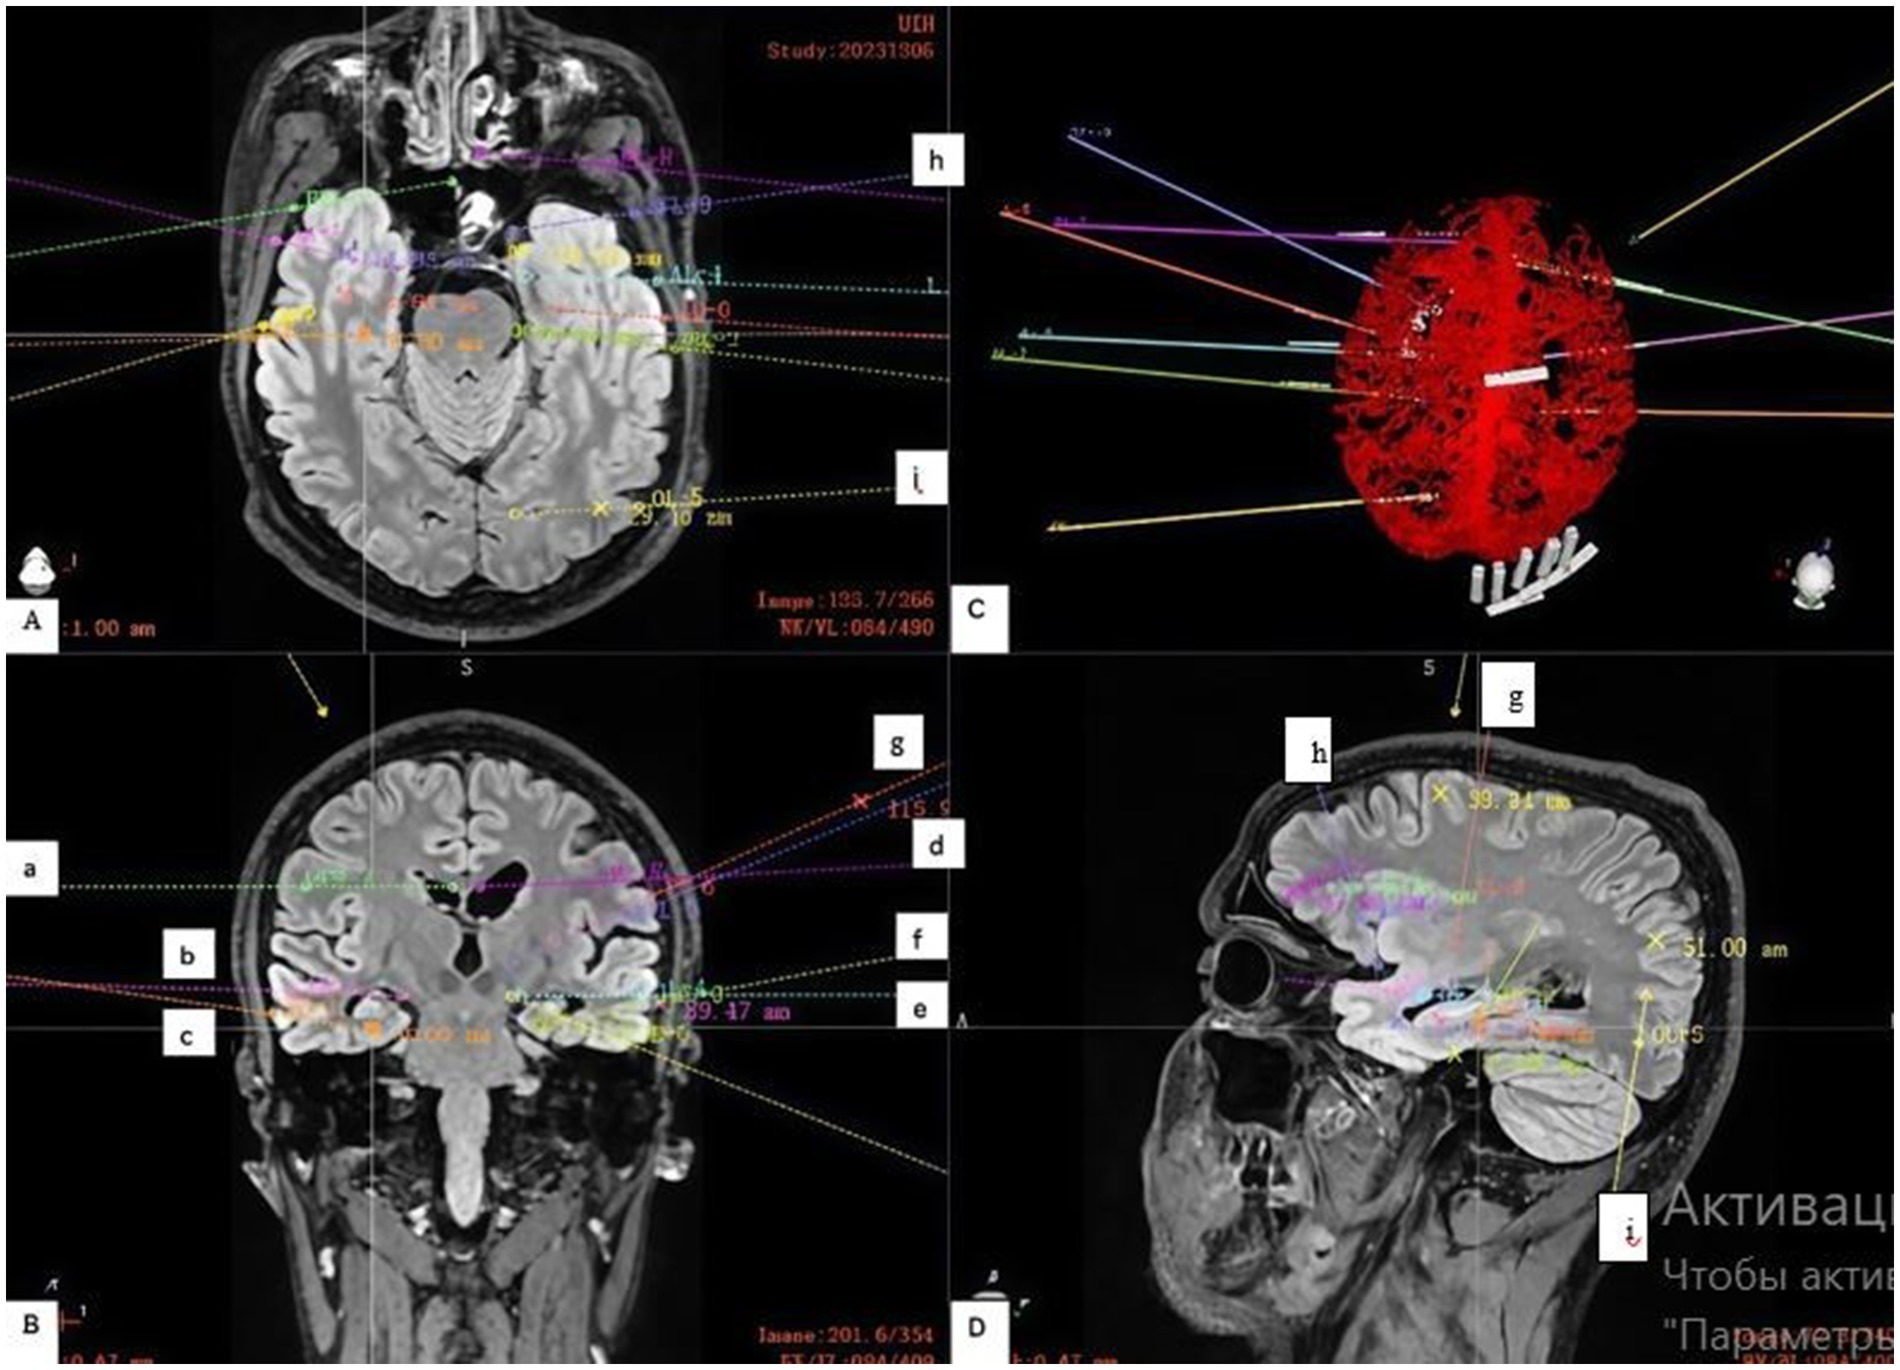

Electrodes implanted bilaterally in the hippocampus (c, f), amygdala (b, e) and cingulate gyrus (a, d) formed the basis of the study (Figure 2). These three structures are key nodes of the mesial temporal (limbic) network. The presence of bilateral hippocampal sclerosis on MRI and temporal onset of seizures on EEG made it necessary to study these structures in both hemispheres. The aim was both to determine the independent onset of seizures in each hippocampus and to assess the possible role of the amygdala and cingulate gyrus as areas of early spread or independent foci.

Figure 2. Stereoelectroencephalography (SEEG) Electrode Implantation Strategy. (A) Shows an axial view of the trajectories, targeting the: (h) left orbitofrontal cortex and (i) left occipital lobe. (B) Shows a coronal view with electrodes placed in key limbic structures: (a) right cingulate gyrus, (b) right amygdala, (c) right hippocampus; and (d) left cingulate gyrus, (e) left amygdala, (f) left hippocampus; and (g) left insular gyrus. (C) Demonstrates the planned electrode trajectories relative to the brain’s vascular structures, as confirmed by a contrast-enhanced computed tomography (CT) scan. (D) On the sagittal projection, the trajectory of the electrodes in the left hemisphere directed to the (h) orbitofrontal cortex, (g) insular gyrus; and (i) occipital lobe is more clearly visible.

Limited implantation in the right hemisphere was aimed at testing the hypothesis of its role, while denser coverage of the left hemisphere was necessary for detailed mapping of the more suspicious side.

Since the scalp EEG indicated a more complex and extensive network in the left hemisphere (only left-sided seizures led to generalization), additional key nodes were investigated (Figure 1).

Insular gyrus (g): Given the ability of insular seizures to mimic temporal or frontal seizures, as well as the patient’s complex semiology, examination of this deep structure was necessary to rule it out as the primary source of pathological activity.

Basal lobe/orbitofrontal cortex (h): Frontotemporal leads on the scalp EEG showed pathological activity. The orbitofrontal cortex has very close anatomical and functional connections with the mesial temporal structures (especially the amygdala). Seizures can spread very quickly between these areas.

Occipital lobe (i): The electrode was placed to determine the posterior boundary of the epileptogenic network. Given that hippocampal seizures often spread posteriorly along the temporo-parieto-occipital junction, understanding the posterior boundary of pathological activity is critical for planning a safe and effective operation (resection or neuromodulation).

The electrodes were implanted via a frameless robotic navigation technique utilizing the Remebot system. Pre-operative planning was meticulously executed, integrating high-resolution computed tomography (CT) and magnetic resonance imaging (MRI) data (Figure 2). Crucially, contrast-enhanced CT scans were incorporated into the planning phase to facilitate precise trajectory adjustments and mitigate the risk of vascular injury, which allowed us to successfully avoid damage.